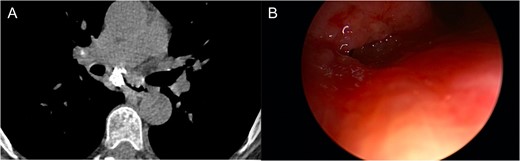

One-year after her original presentation, the patient presented to the emergency room with worsening cough and choking with oral intake. A CT scan of chest revealed a fistula between the right mainstem bronchus and esophagus (Fig. 2A). The patient underwent rigid bronchoscopy revealing a 2-cm defect on the medial wall of the right mainstem bronchus, ~1-cm from the main carina (Fig. 2B). A CT esophagram confirmed extravasation of oral contrast into the tracheobronchial tree (Fig. 3).

(A) CT scan revealing fistula between the right mainstem bronchus and esophagus. (B) Endobronchial view visualizing right mainstem defect.